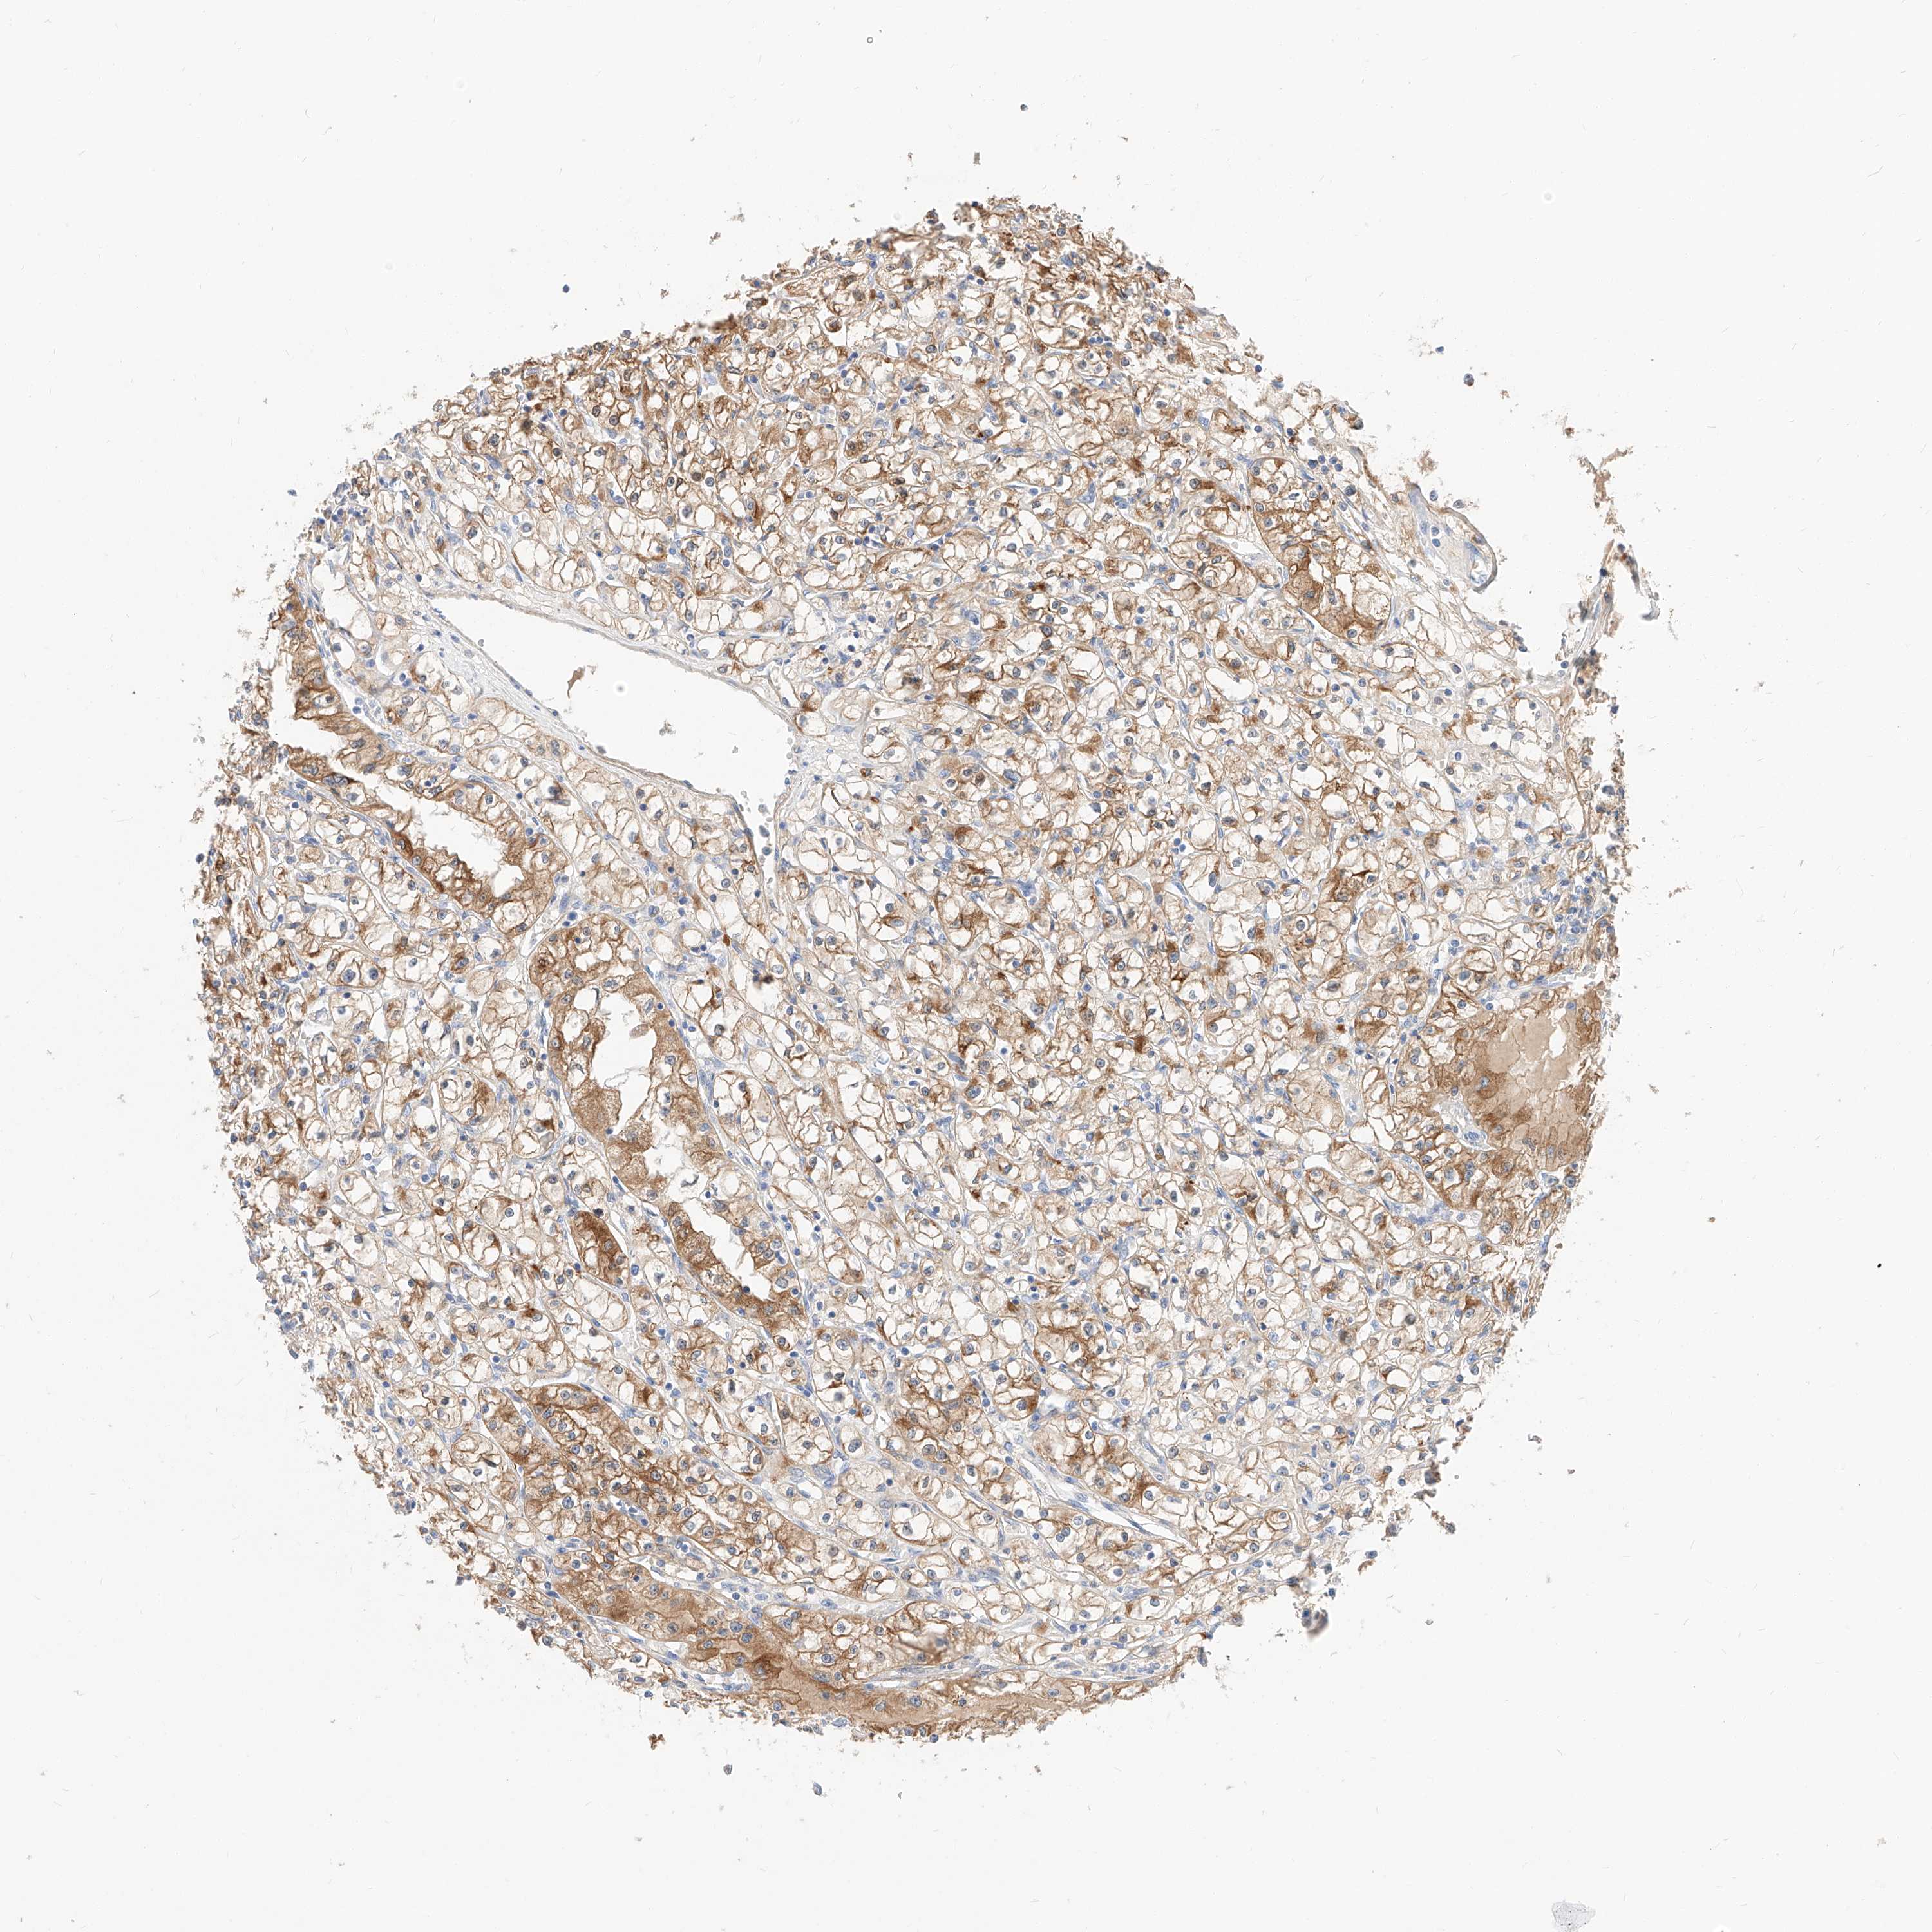

KIDNEY RENAL PAPILLARY CELL CARCINOMA (TCGA) - Interactive survival scatter ploti

The Survival Scatter plot shows the clinical status (i.e. dead or alive) for all individuals in the patient cohort, based on the same data that underlies the corresponding Kaplan-Meier plots. Patients that are alive at last time for follow-up are shown in blue and patients who have died during the study are shown in red.

The x-axis shows the expression levels (FPKM) of the investigated gene in the tumor tissue at the time of diagnosis. The y-axis shows the follow-up time after diagnosis (years). Both axes are complimented with kernel density curves demonstrating the data density over the axes. The top density plot shows the expression levels (FPKM) distribution among dead (red) and alive patients (blue). The right density plot shows the data density of the survived years of dead patients with high and low expression levels respectively, stratified using the cutoff indicated by the vertical dashed line through the Survival Scatter plot. This cutoff is automatically defined based on the FPKM cutoff that minimizes the p-score. The cutoff can be changed by dragging the vertical line or by entering a cutoff value in the square labeled "Current cut-off".

Under the Survival Scatter plot the p-score landscape (black curve; left axis) is shown together with dead median separation (red curve; right axis). Dead median separation is the difference in median mRNA expression between patients who have died with high and low expression, respectively. It is calculated as follows: median FPKM expression of dead patients with high expression - median FPKM expression of dead patients with low expression. This is intended to aid the user in visually exploring custom cutoffs and the associated p-scores and dead median separation.

Individual patient data is displayed and can be filtered by clicking on one or more of the category buttons on the top of the page. Categories describing expression level and patient information include: high, low, alive, dead, female, male and tumor stages. The scale of the x-axis can be toggled between linear and log-scale by clicking on the "x log" button. Mouse-over function shows TCGA ID, patient information and mRNA expression (FPKM) for each patient.

& Survival analysisi

Kaplan-Meier plots summarize results from analysis of correlation between mRNA expression level and patient survival. Patients were divided based on level of expression into one of the two groups "low" (under cut off) or "high" (over cut off). X-axis shows time for survival (years) and y-axis shows the probability of survival, where 1.0 corresponds to 100 percent.

MAP7 is not prognostic in Kidney Renal Papillary Cell Carcinoma (TCGA)